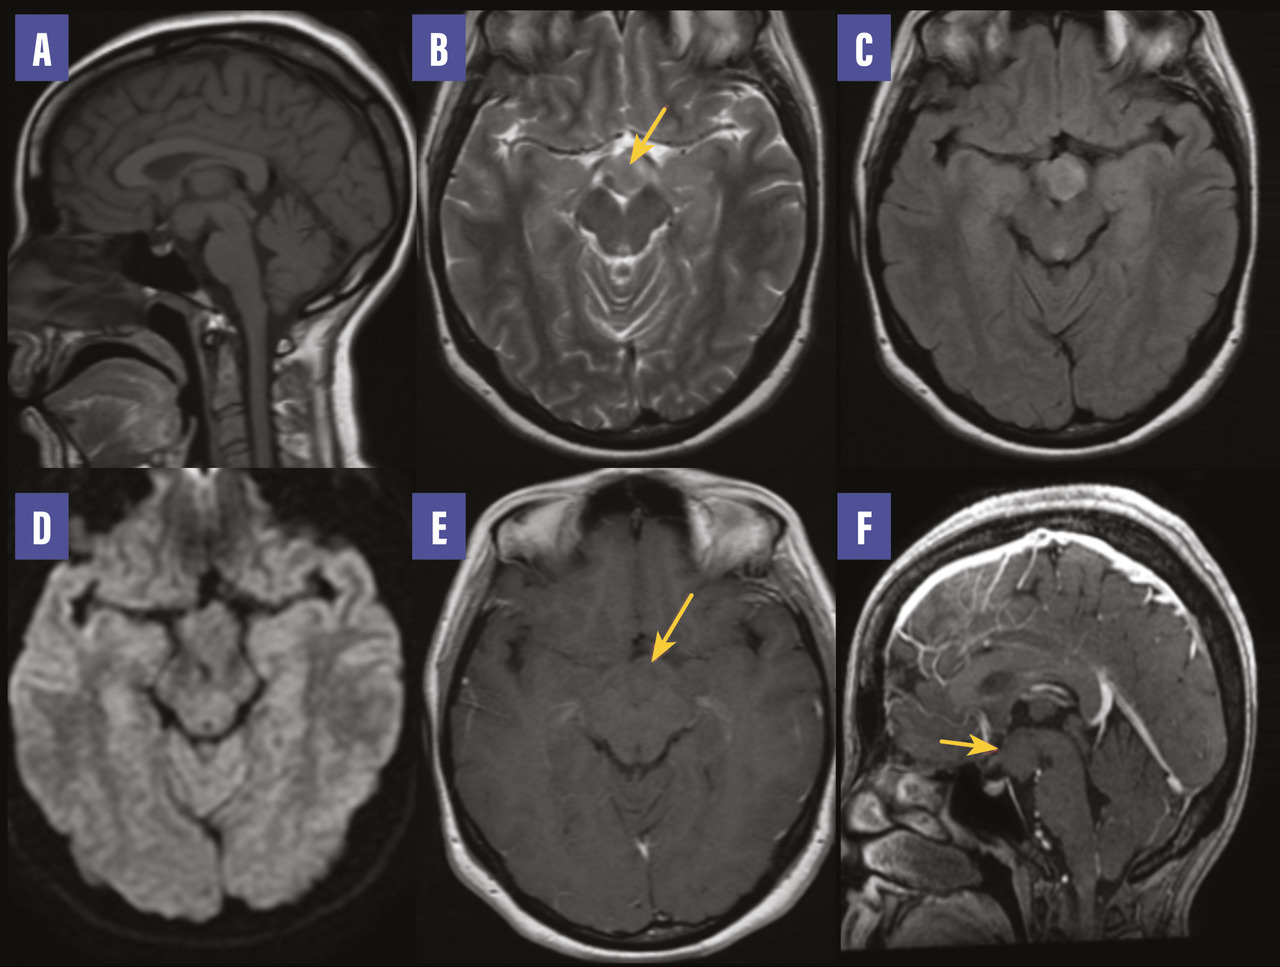

Imagerie par résonance magnétique cérébrale : sagittal T1 (A), axial T2 (B), FLAIR (C), diffusion (D), T1 après injection (axial et sagittal) [E, F]. Formation hypothalamique en isosignal T1, hypersignal T2 et FLAIR sans hypersignal diffusion et sans rehaussement après injection de chélates de gadolinium.